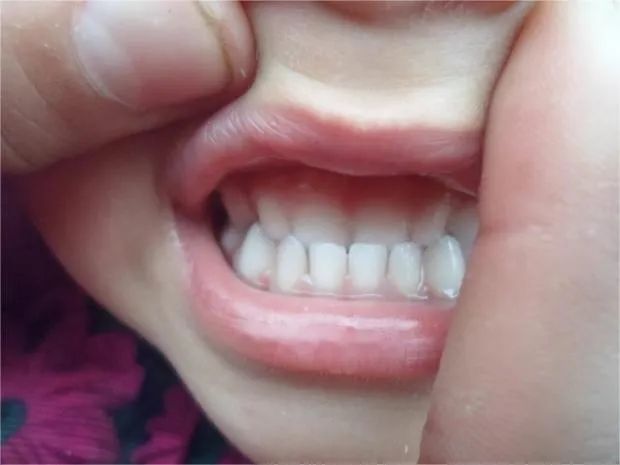

地包天面型一般是上前牙唇倾,下前牙明显舌倾。且大样本量的日本骨性地包天儿童人群研究显示,6~16岁之间,12~16 岁青少年的反地包天严重程度远远大于 5~11 岁的儿童。也就是说地包天下颌骨长度会随着年龄逐渐增加。

就像这个小朋友初诊检查头侧片子发现骨骼I类、牙齿III类咬合关系。但是,孩子家长拒绝接受治疗,觉得孩子换完牙就变好了,不会变成严重的地包天问题。

但是1年半之后,孩子前牙地包天问题加重,下颌前凸也很明显,这才又想要通过牙齿矫正改善孩子的牙齿咬合和面型情况。